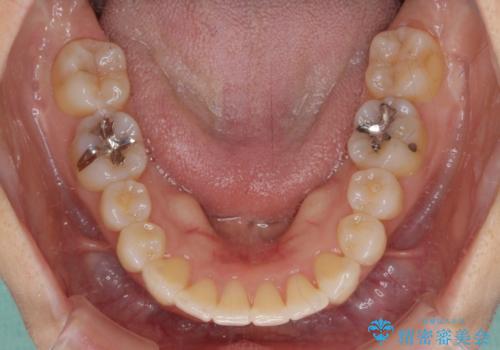

- 前歯の捻れと、それに伴う口元の突出感を気にして来院された患者様です。

早く治療を終えたいとのことで、ワイヤー装置による矯正治療を行うこととしました。

上顎前歯の叢生が解消されると出っ歯になることが分かっていたので、両側奥歯付近にアンカースクリューを入れ、出っ歯を改善するためのゴムかけを行いました。

ゴムかけを頑張っていただいたので、当初の予定通り、1年強で治療を終えることができました。